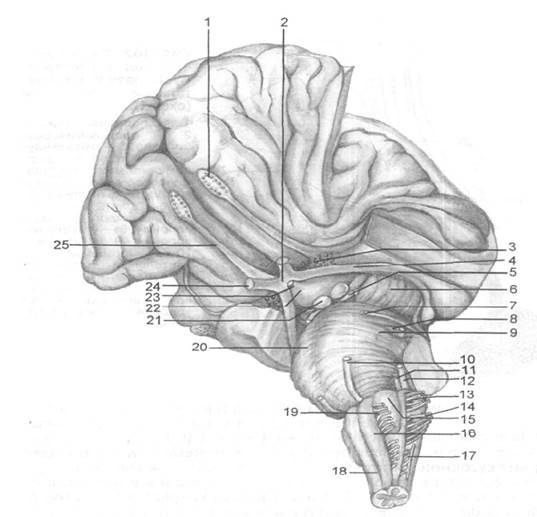

Необычные объекты: Переднее продырявленное вещество